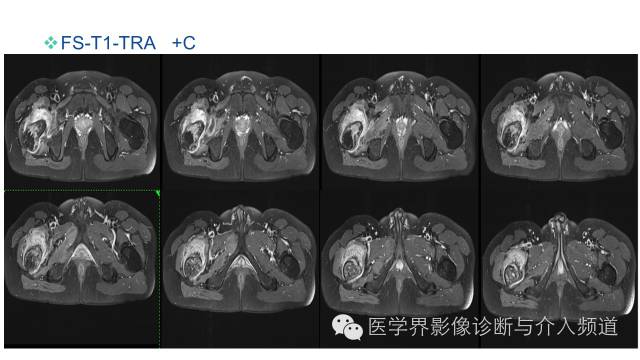

MR平扫及增强示:

右侧股骨上段见不规则形长T1短等T2异常信号,直径约1.5cm,邻近骨皮质破坏,其内骨髓可见斑片状长T1等长T2混杂信号,边界不清,股前方可见软组织肿块,呈长T1等长T2混杂信号,DWI呈明显高信号;注入GD-DTPA后,股骨内病灶呈轻度强化,周围软组织呈明显不均质强化。左侧髋关节诸组成骨对位关系可,未见明显骨质破坏征象,双侧髋关节可见少量斑片状长T2液体信号影。